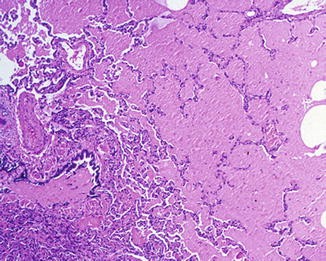

Para confirmar el diagnóstico de proteinosis alveolar, se realiza un procedimiento llamado lavado broncoalveolar (BAL). Durante este procedimiento, un líquido se introduce en los pulmones a través de un broncoscopio y luego se recoge para su análisis. En la proteinosis alveolar, este líquido tiene una apariencia lechosa debido a la alta concentración de material lipoproteináceo. Además, el material lipoproteináceo se tiñe con una técnica llamada ácido-Schiff (PAS), lo que ayuda a visualizarlo bajo el microscopio y confirmar su presencia.